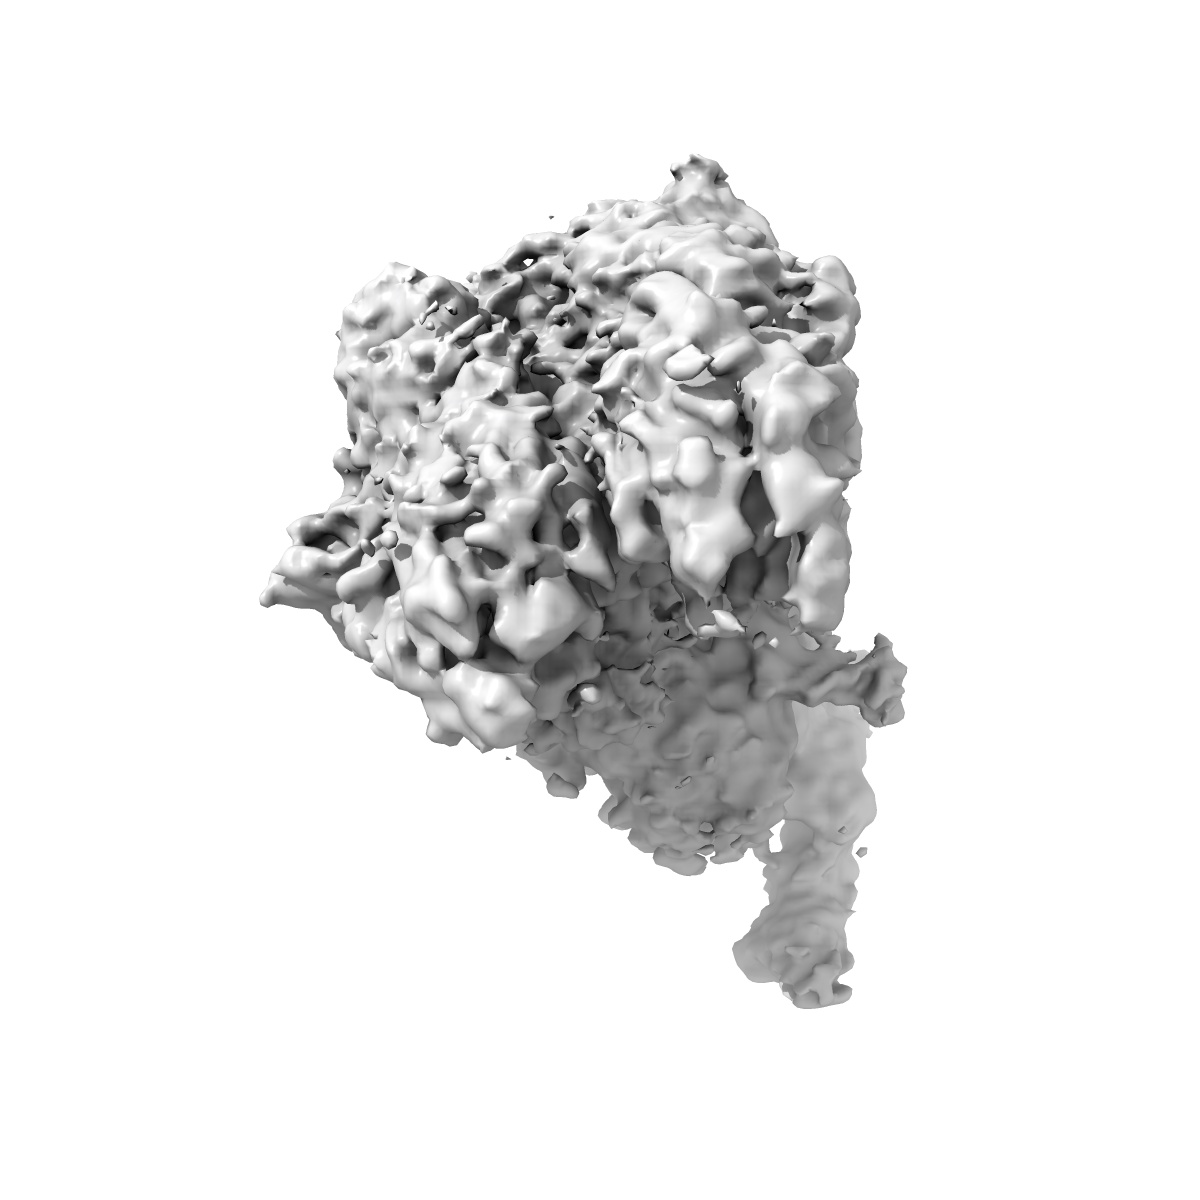

Cryo-EM structure of factor Va bound to activated protein C

Cryo-EM structure of coagulation factor Va bound to activated protein C.